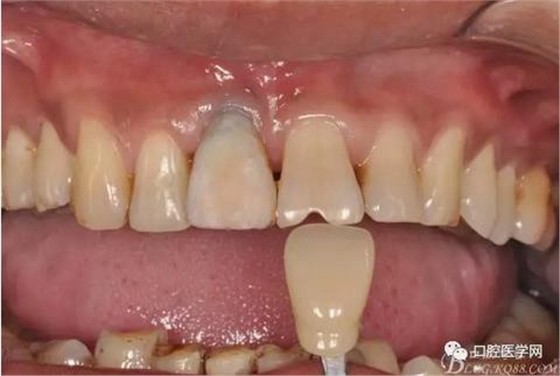

圖4 術(shù)前正位頜面照

圖8 術(shù)后即刻臨時(shí)冠修復(fù)

圖9 三個(gè)月后袖口形成正位照